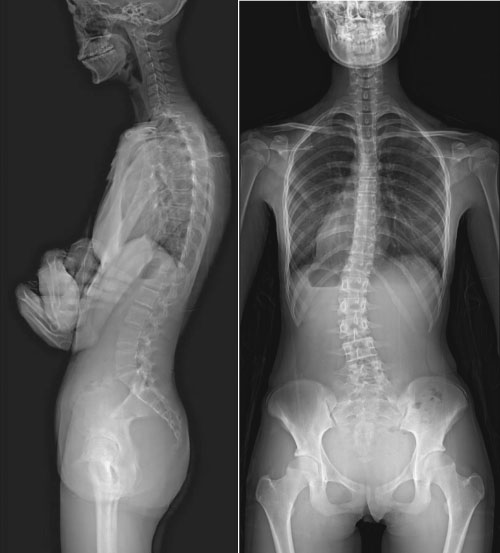

SONIALVISION C200 是一款数字化X射线透视摄影系统,适应多种临床环境,可满足放射科的多科室检查需求。

满足全科检查的多功能设计

多种独特的运动方式,可以应用于各种复杂检查。